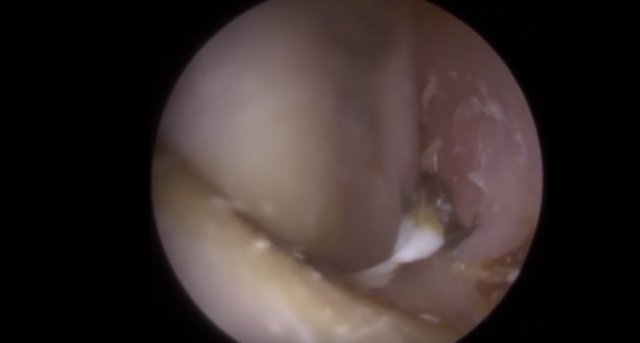

30 yıl boyunca geçmeyen bir baş ağrısı ile yaşayan bir kişi gittiği doktoru şoke etti. Yıllarca baş ağrısı çeken 59 yaşındaki adamın yaşadıkları kan dondurdu. Adamın kafasından öyle bir şey çıktı ki, doktorlar bile şaştı kaldı. İşte şoke eden olayın detayları...